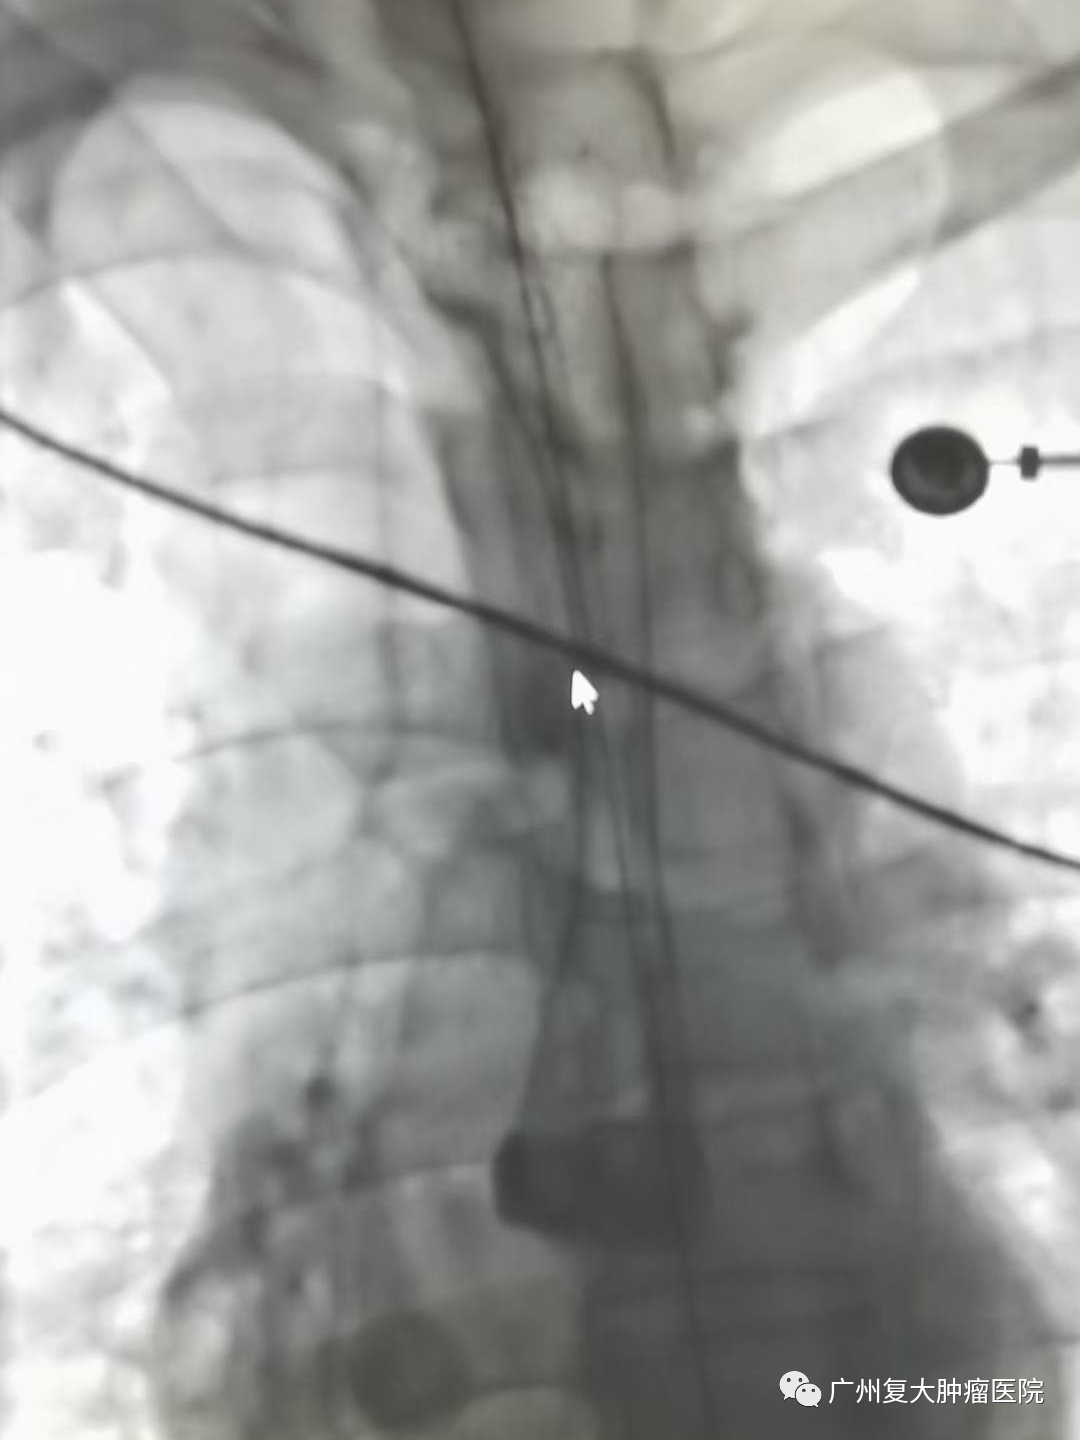

新年伊始,牛立志院长和介入科钟小军医生等医护人员在查房的过程中,收到一名食道癌患者满满的祝福。患者因食道癌并食道-气管瘘在多家大医院寻医问诊,但因带胃管两个多月,进食困难,精神萎靡,生活质量较差。为进一步诊疗,于年前28日晚来到我院,并在隔天完善相关检查后接受食道全覆膜支架置入。术后第一天便可以进食水,精神状态也明显好转。恰逢元旦来临,患者在院感受节日氛围的同时,身体状况也愈来愈好,对他们一家人来说,这不仅是最好的新年礼物,也让他们对新的一年充满新希望。为此,患者把自己亲手写的祝福送给医护人员,以表感谢之情。